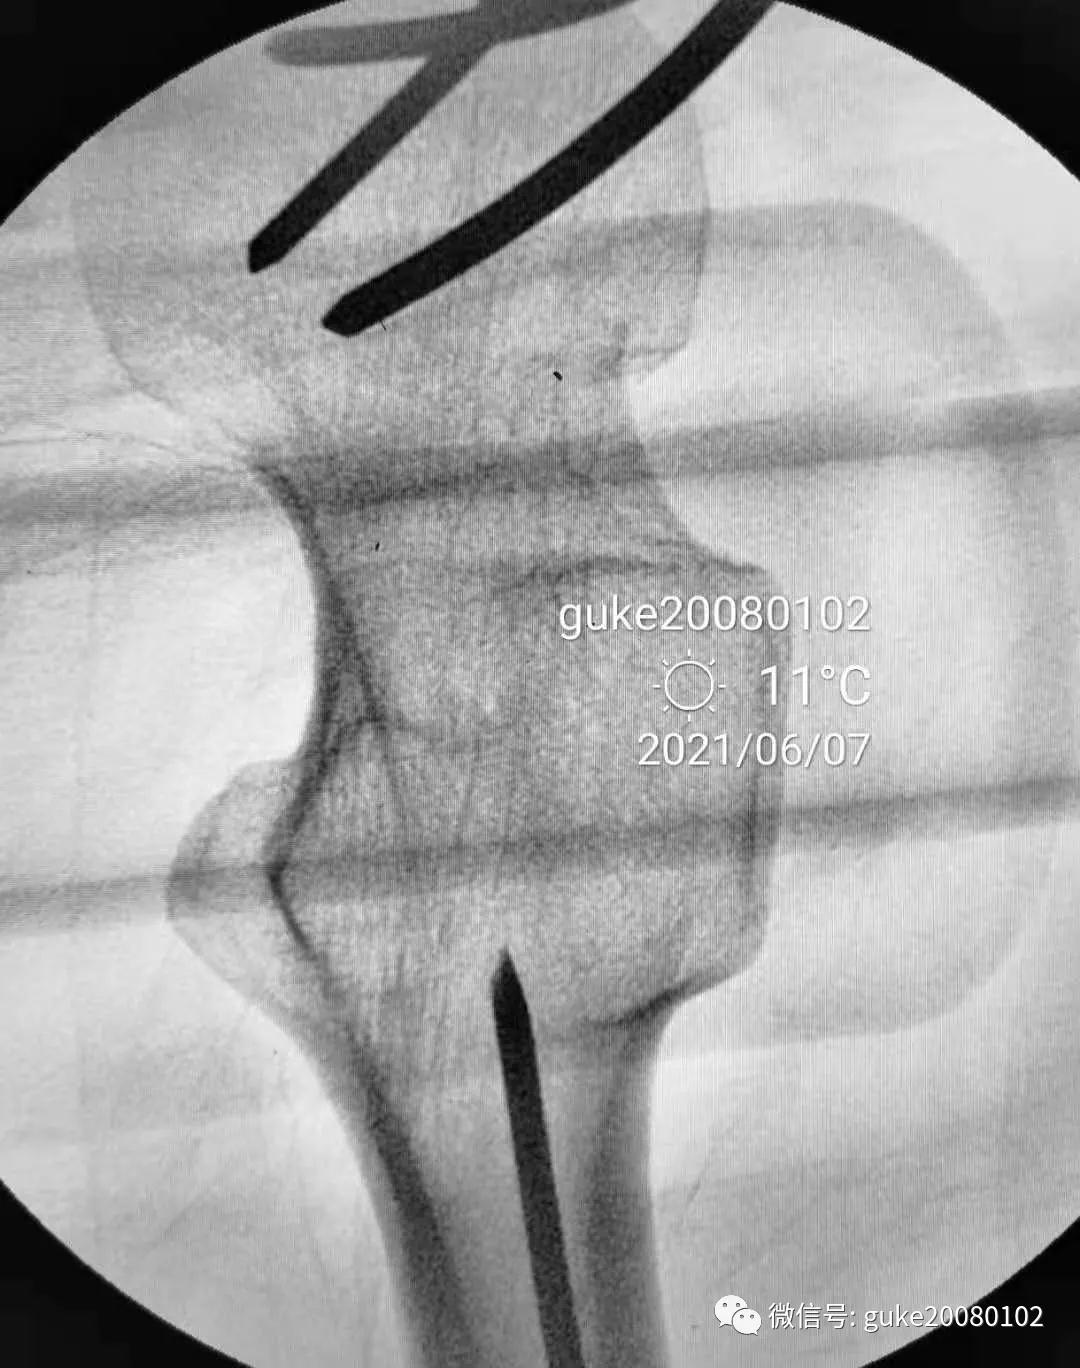

1、植入的第一枚克氏针,前倾和颈干角均满意。将其作为标志针。

2、植入第二枚导针,调整前倾和颈干角。

3、数次调整三枚导针到最合适的位置。